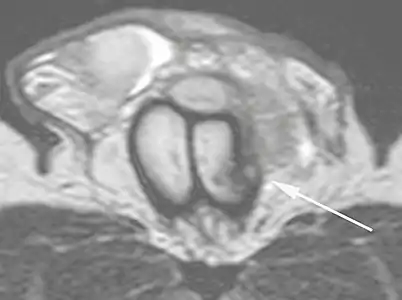

În examinarea cu ultrasunete, o leziune a tunicii albuginea se prezintă ca o întrerupere a (pierderii continuității) liniei ecografice care o reprezintă (Figura 4). Hematoamele mici, moderate sau mari demonstrează gradul de discontinuitate. Hematoamele intracavernoase, uneori fără prezența unei fracturi a tunicii albuginea, pot fi observate atunci când există o leziune a mușchiului neted al trabeculelor care înconjoară spațiile sinusoidale sau plexul venular subtunical. [10]

Figure 4 A: Ultrasound of the penis, right lateral view. Longitudinal section showing rupture of the tunica albuginea with an adjacent 1.92 cm hematoma (between calipers), due to trauma.[10]

B: Axial T2-weighted turbo spin-echo magnetic resonance imaging scan showing left-sided discontinuity of the tunica albuginea (arrow), secondary to fracture.[10]